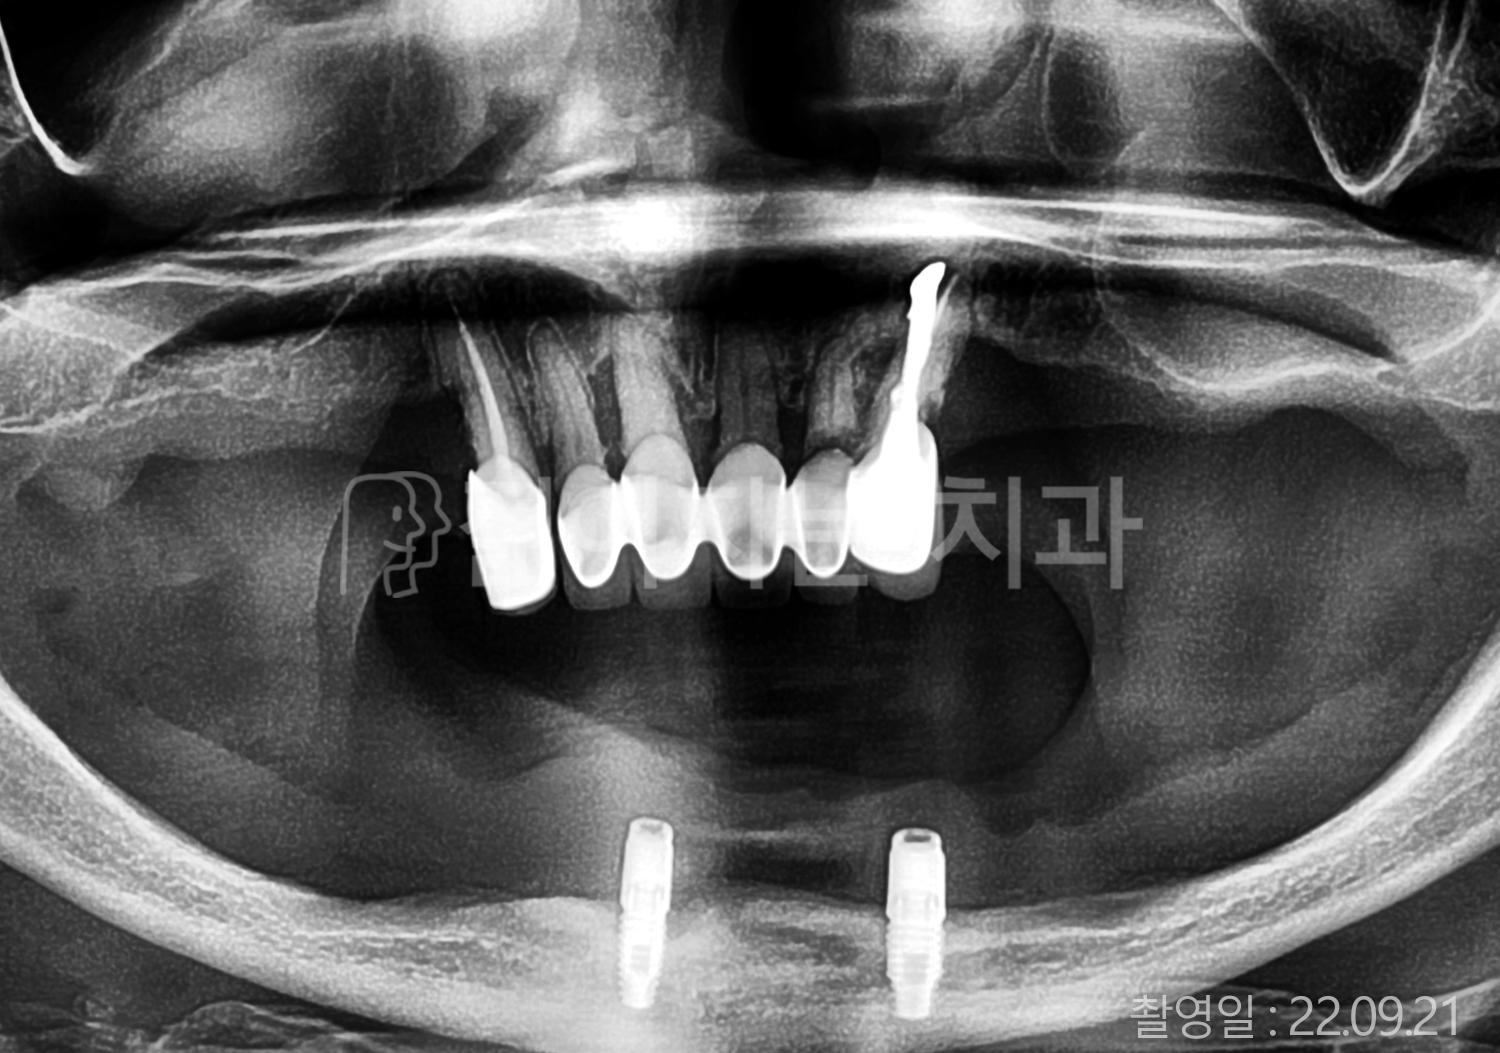

• 50대 고혈압, 당뇨, 고지혈증 전체치아 10개 이상 임플란트

• 60대 골다골증, 간경화 전체치아 10개 이상 임플란트

• 60대 고혈압, 고지혈증 전체치아 10개 이상 임플란트

• 50대 고혈압, 당뇨 전체치아 10개 이상 임플란트

• 60대 고혈압 전체치아 10개 이상 임플란트

• 60대 전체치아 10개 이상 임플란트

• 60대 고지혈증 전체치아 10개 이상 임플란트

• 40대 전체치아 10개 이상 임플란트

• 70대 전체치아 10개 이상 임플란트